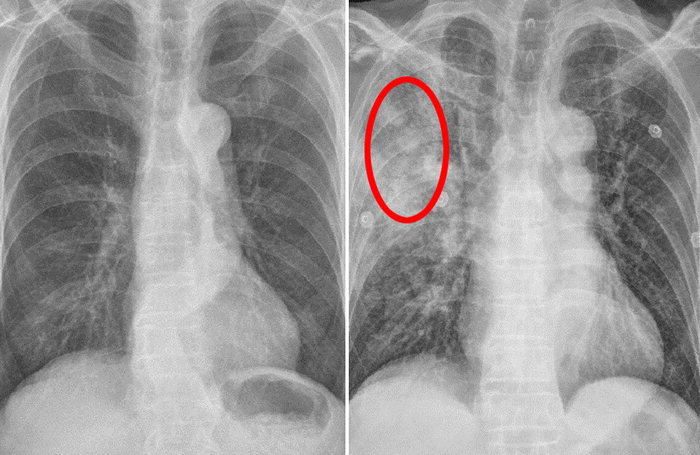

이러한 폐암의 원인으로 인해 폐암으로 진단되기 전에 폐암 초기증상을 조기에 발견하면 다른 장기로의 전이나 진행성 폐암으로의 진행을 어느 정도 지연시키거나 적절하게 치료할 수 있지만 일반적으로 폐암의 초기 단계는 특별한 징후나 증상이 없으므로 조기에 발견하는 경우는 극히 드뭅니다.

폐암 초기증상

잦은 기침

폐암 초기에는 기침이 잦거나 가래가 끓는 등 감기와 같은 증상이 나타날 수 있다. 따라서 폐암은 초기에 암인지 판단하기 어렵다. 또한 객담이나 적혈구를 동시에 토하는 것도 폐암을 진단하는 가장 중요한 증상 중 하나이다. 붉은 피가 섞인 가래 증상이 있으면 병원에 가서 검사를 받아야 한다.

또는 가래, 기침, 목소리가 쉬지 못하는 등 가벼운 감기라고 생각하여 폐암이 진행된 후에 종양이 발견되는 경우가 많습니다. 폐렴은 또한 기관지의 감염성 종양을 동반할 수 있습니다. 또한, 그럼에도 불구하고 폐렴만을 중심으로 치료를 하다 보면 상세한 검사 결과로 인해 종양을 식별하지 못하거나 폐암으로 발전할 수 있습니다.